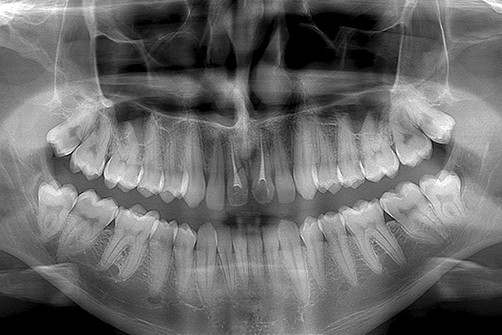

Umożliwia on wykonanie zdjęć panoramicznych – OPG, które uwzględniają obraz całości kości szczęk i żuchwy, całego uzębienia oraz pozostałych szczegółów anatomicznych takich jak zatoki szczękowe, nos, stawy skroniowo żuchwowe oraz oczodoły

Obraz diagnostyczny przedstawiany jest w dwóch wymiarach co ogranicza przestrzenną analizę interesującego nasz obszaru anatomii pacjenta. Zdjęcie panoramiczna w połączeniu z klinicznym badaniem jamy ustnej pacjenta daje pełną, podstawową informację odnośnie diagnozowanego obszaru.

Zdjęcie pantomograficzne, zwane również panoramicznym, to specjalistyczne badanie obrazowe używane do celów stomatologicznych. Wykonujemy je, gdy istnieje potrzeba zobrazowania wszystkich zębów szczęki i żuchwy (również tych zatrzymanych), zatok szczękowych, stawów skroniowo-żuchwowych, a także otaczających tkanek.

Wykonujemy je, ustawiając pacjenta przed kolumną aparatu, następnie polecamy, aby zagryzł specjalny ustnik, przez co uzyskujemy właściwą pozycję głowy, która gwarantuje odpowiednią projekcję. Podczas badania należy przez kilka sekund zachować bezruch oraz wykonywać polecenia technika. W trakcie badania głowica pantomografu krąży wokół głowy pacjenta przez kilka sekund, a uzyskany obraz jest od razu widoczny na monitorze.